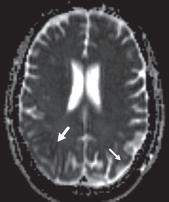

在 CT 上,小血管缺血性疾病表现为小穿支动脉区域皮质下和脑室周围白质的多发性白质低密度影。基底神经节和幕上区域也可见局灶性腔隙(图 5A )。高血压患者常见的自发性出血,一般位于基底节或丘脑。在存在败血症或先天性心脏病的情况下,栓子也会在血管区域之间的边界处产生分水岭梗塞。MRI 显示缺血区域在 T2/FLAIR呈现 高信号(图 5B ))。扩散受限存在于急性期,但在亚急性期和慢性期正常化。

图 5A——小血管缺血性疾病。半卵圆中心水平的平扫 CT 图像显示弥漫性皮质下白质低密度以及代表腔隙的更多局灶性低密度(箭头)

图 5B —小血管缺血性疾病。FLAIR 图像显示多个脑室周围高信号灶。